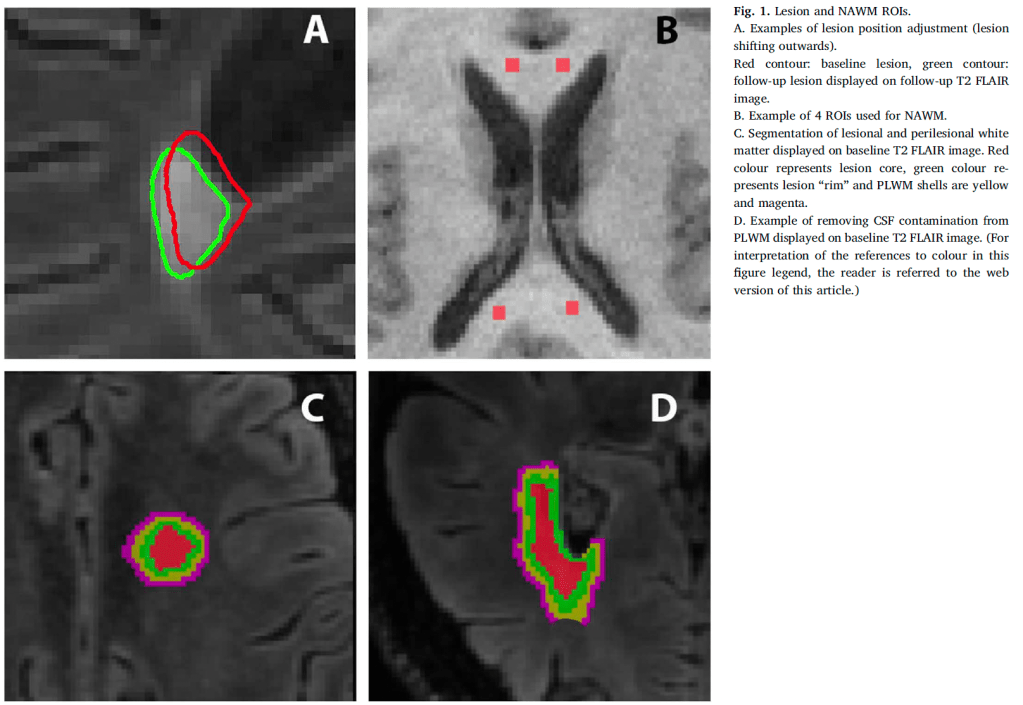

- Developed methods to precisely analyze lesion cores separate from edges